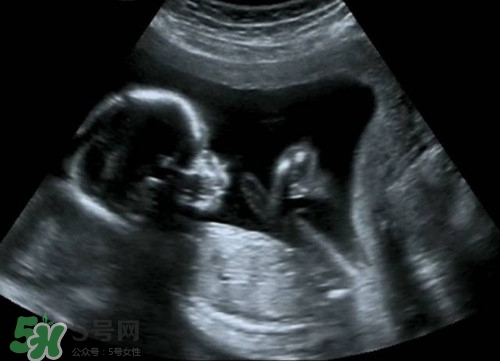

懷孕之后b超肯定是要做的,那么懷孕多久后可以做b超呢?做b超的話會影響到孩子嗎?下面我們來一起介紹下吧!

孕期做B超檢查是很有必要的.但是孕期做B超不要超過3次.一般是懷孕早期應(yīng)通過B超確定宮內(nèi)的妊娠是否正常.一般提倡于懷孕早期通過做B超明確是否是宮內(nèi)正常妊娠或雙胎,葡萄胎等.懷孕中期,大約在閉經(jīng)16周左右需要再做一次B超,以確定胎兒有無畸形和生長發(fā)育是否正常.因?yàn)槿绻@時發(fā)現(xiàn)胎兒不正常,在閉經(jīng)20周以內(nèi)中止妊娠,是比較適宜的.懷孕晚期,即閉經(jīng)36周以后,做B超可以明確羊水多少以及胎盤的功能.羊水過多或過少,以及胎盤鈣化或功能不良,都不應(yīng)再繼續(xù)妊娠.必要時需進(jìn)行剖腹產(chǎn)

目前臨床上所應(yīng)用的B超,其探頭發(fā)射的聲強(qiáng)度小于10毫瓦/平方厘米,而且超聲檢查的時間往往只有5~10分鐘,對每個器官的探測時間更短.所以說,B超檢查對胎兒的危害是極小的,不會影響胎兒的身心發(fā)育.因此,孕婦不必對孕期B超檢查產(chǎn)生恐懼心理,適時的B超檢查是確保胎兒正常發(fā)育的重要手段.